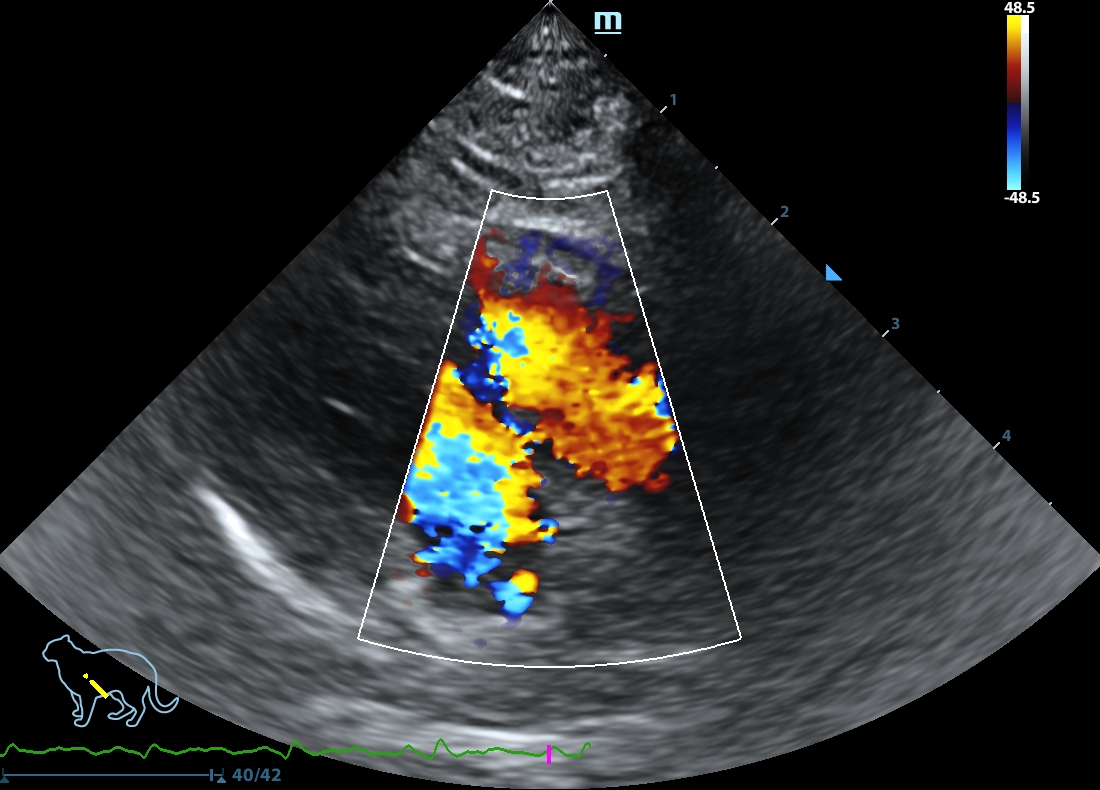

202505231605100136CARD.JPG